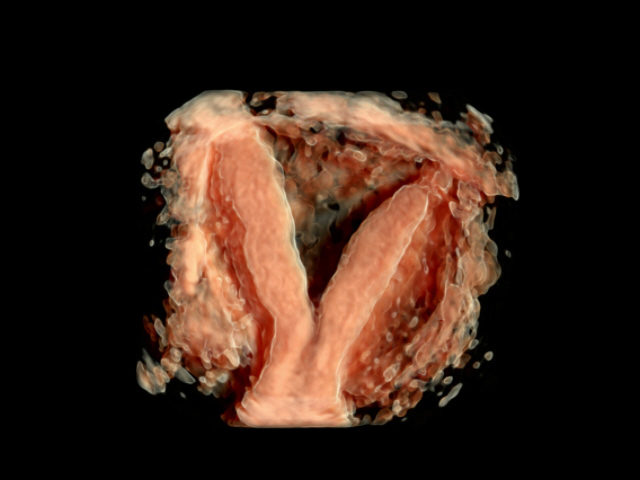

✔️ Standard Pelvic Scan – 2D / 3D in gynecological health and disease

✔️ Ultrasound assessment to plan management of uterine fibroids, uterine anomalies by 2D / 3D / Power Doppler Study